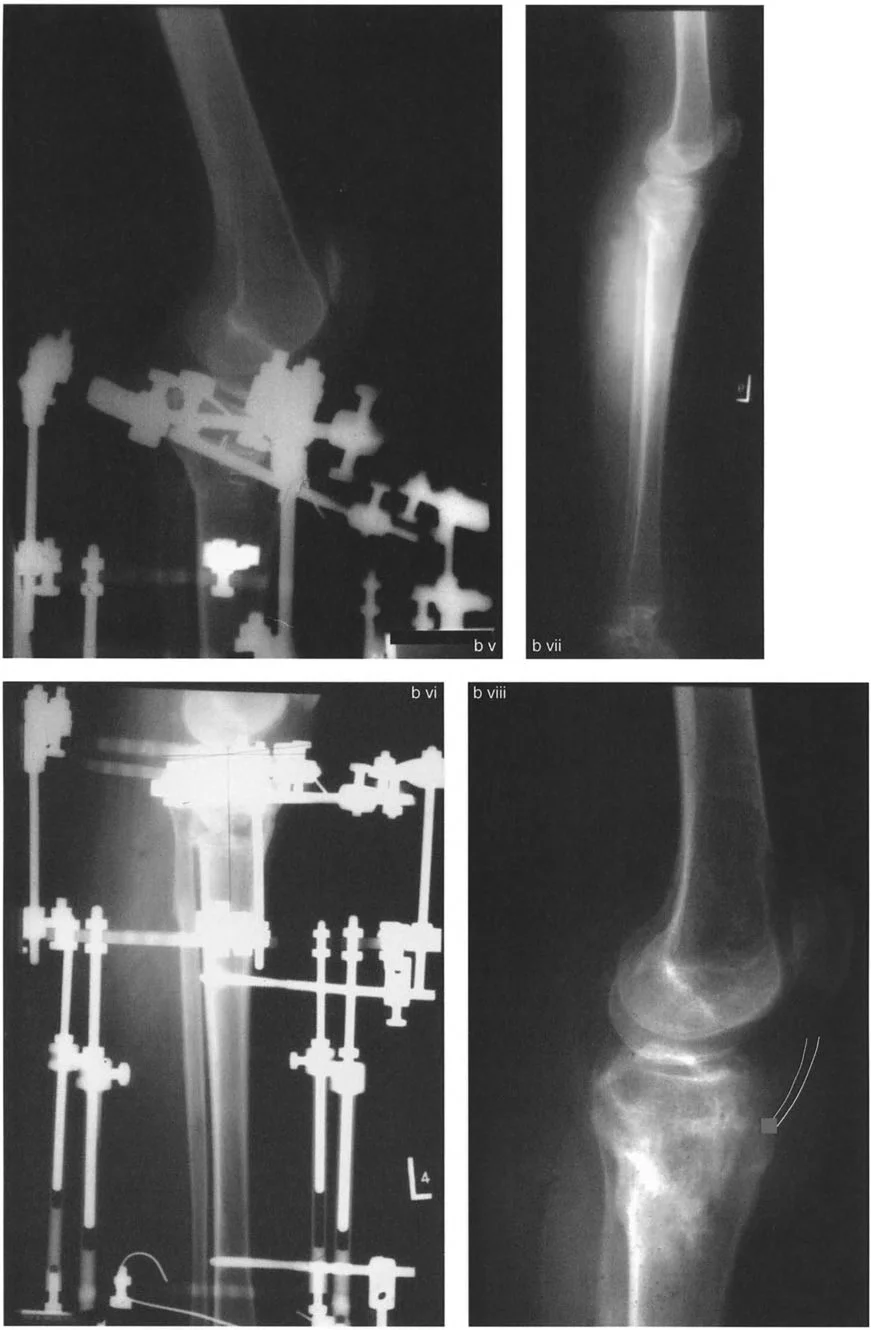

- تصحيح الفخذ: يتم إجراء قطع عظمي على شكل إسفين إغلاق أو إسفين فتح في الفخذ عند نقطة CORA. غالباً ما يتم تثبيت هذا بإبرة نخاعية (IMN) أو صفيحة تثبيت قوية.

- تصحيح الظنبوب: قد تتضمن عملية ثانوية قطع عظمي أسفل الحدبة الظنبوبية لتصحيح التشوه التعويضي في الجزء القريب من الظنبوب.

- نقل الرضفة: إذا كان هناك انخفاض ثانوي في الرضفة (غالباً بسبب ميكانيكا متغيرة طويلة الأمد أو جراحات سابقة)، يمكن نقل الرضفة للأعلى باستخدام مثبت خارجي (مثل جهاز إليزاروف أو إطار تايلور الفراغي) لاستعادة التوتر الطبيعي لآلية الباسطة.

تُظهر الصورة تشوه التقوس الأمامي في عظم الفخذ وكيف يؤثر على محاذاة الركبة، مما يستدعي تدخلاً جراحياً دقيقاً.

- التثبيت: يتيح استخدام جهاز إليزاروف أو إطار دائري سداسي الأرجل تصحيحاً تدريجياً ومتحكماً للتقوس الخلفي. توفر الأسلاك الدقيقة تثبيتاً ممتازاً في الجزء المفصلي القريب الصغير.

تُظهر الصورة تخطيطاً لقطع العظم على شكل حرف L، وهي تقنية معقدة تستخدم لتصحيح التقوس الخلفي بعد كسور هضبة الظنبوب.

تُظهر هذه الصورة نتائج جراحة قطع العظم على شكل حرف L، مع استعادة المحاذاة التشريحية للركبة.

يتضمن التصحيح قطع عظمي دقيق على شكل إسفين فتح فوق الحدبة الظنبوبية، جنباً إلى جنب مع نقل الظنبوب للأسفل باستخدام إطار دائري. يحقق هذا تقليلاً غير مباشر للظنبوب، ويحل تماماً خلع الركبة الجزئي والتقوس الخلفي مع الحفاظ على ارتفاع الرضفة الطبيعي.

تُوضح الصورة كيفية تصحيح التقوس الخلفي الناتج عن العلاج الإشعاعي باستخدام جهاز إليزاروف، مما يحقق محاذاة طبيعية للركبة.